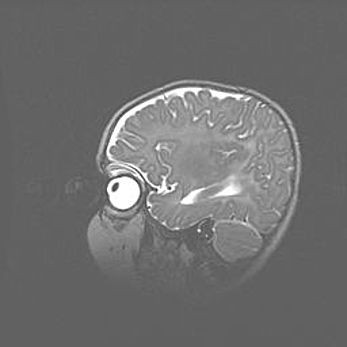

Мальформация Денди-Уокера. Киста задней черепной ямки.

Агенезия мозолистого тела.

Возраст: 2,5 месяца

Вес: 2420 г

Пол: женский

Окружность головы: 37 см

Срок гестации: 32 недели

Мальформация Денди—Уокера — редкий вид патологии ЦНС, представляющий собой врожденный порок развития каудального отдела ствола и червя мозжечка, ведущий к неполному раскрытию срединной (Мажанди) и латеральных (Лушка) апертур IV желудочка мозга. Для этогно синдрома характерна триада симптомов: гипотрофия червя мозжечка и/или полушарий мозжечка, кисты задней черепной ямки, гидроцефалия различной степени. В 70% случаев порок сочетается и с другими аномалиями головного мозга, в частности с агенезией мозолистого тела.